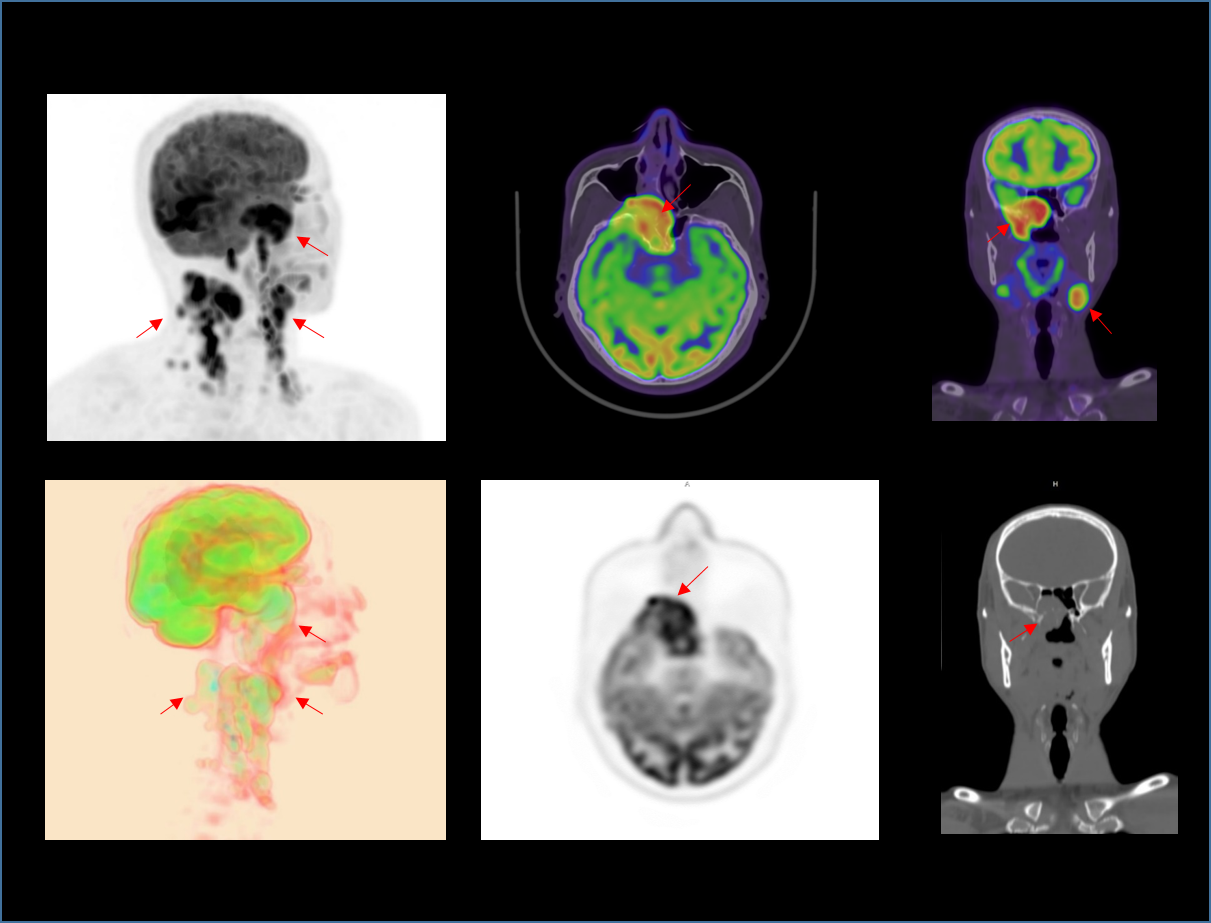

초고 NEMA 해상도

새로운 수준의 혁신적인 분자영상

정밀 영상을 위한 높은 매트릭스 사이즈